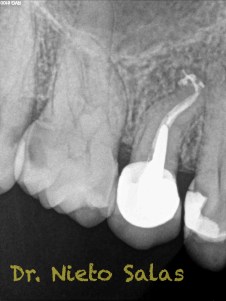

Se nos presenta en la clínica un par de casos de características similares, con lo cual las hemos tratado igual:

Ante estas situaciones, lo que no debemos es intentar llegar a la zona apical rápido, primero prepararemos el tercio medio-coronal, pero sin perder la permeabilidad del conducto con limas de muy pequeños diámetro.

Una vez que tenemos la Long de trabajo, no debemos perderla, se recomienda mucha irrigación e intentaremos que nuestras limas trabajen en una superficie lo menor posible.

Conseguiríamos un sellado de esta manera en el caso A: